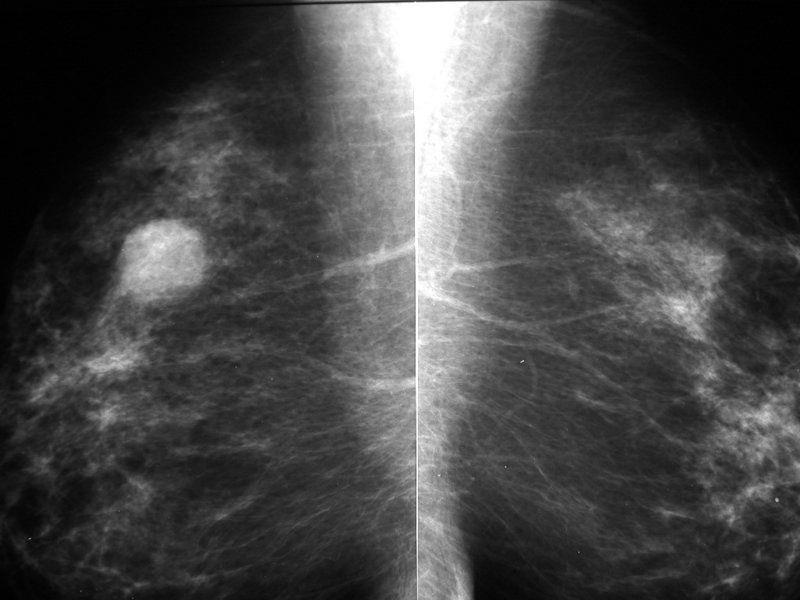

כל שד מצולם בשתי תנוחות – מלמעלה למטה ובאלכסון, וזאת כדי שניתן יהיה לראות היטב מזוויות שונות את כל המבנים בתוכו.ישנם ממצאים הנראים רק בתנוחה אחת, והצילומים בשתי תנוחות לכל שד מאפשרים שלא להחמיץ גילוי ממצאים כאלה.